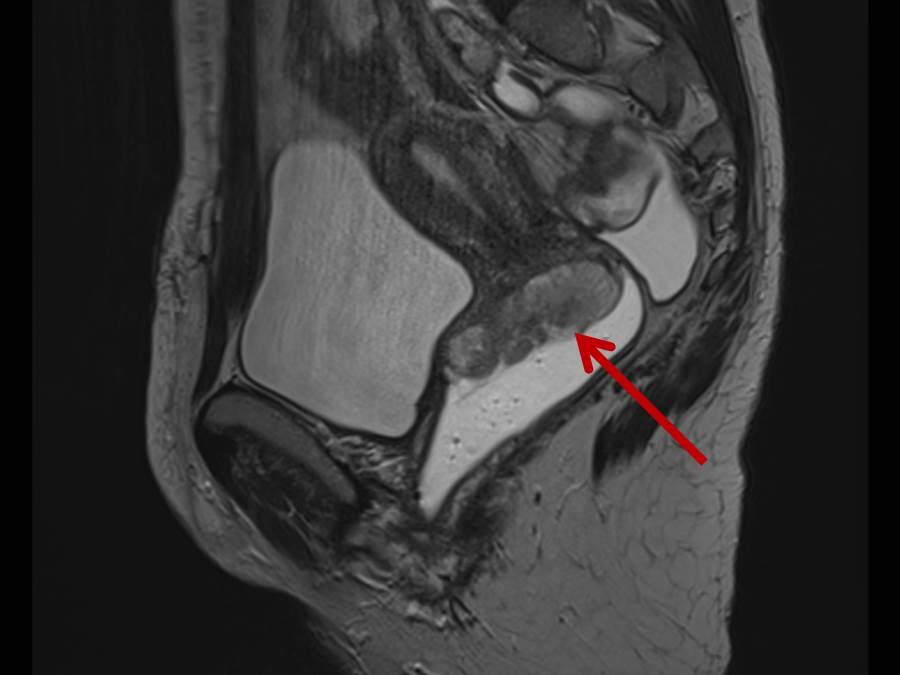

Kann mir jemand helfen beim MRT Bild Becken? (Blase)

Termin beim Orthopäden ist erst in 3 Wochen. Wir von Lumedis haben uns auf die konservative Therapie eines Beckenschiefstandes . Es zeigt sich ein deutliches Knochenmarködem des lateralen Tibiakondylus mit einer eindrucksweise teils . Haben die doch was festgestellt? (siehe Foto) Wer kann mir die Diagnose (Auffälligkeiten) genauer erklären? Verstehe nur Bahnhof.Veröffentlicht auf: July 01, 2024